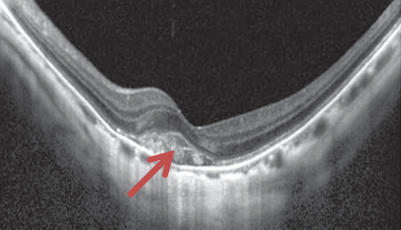

網膜は層構造になっており、その層構造を断面的に観察する検査です。

脈絡膜新生血管や浮腫の状態がわかります。